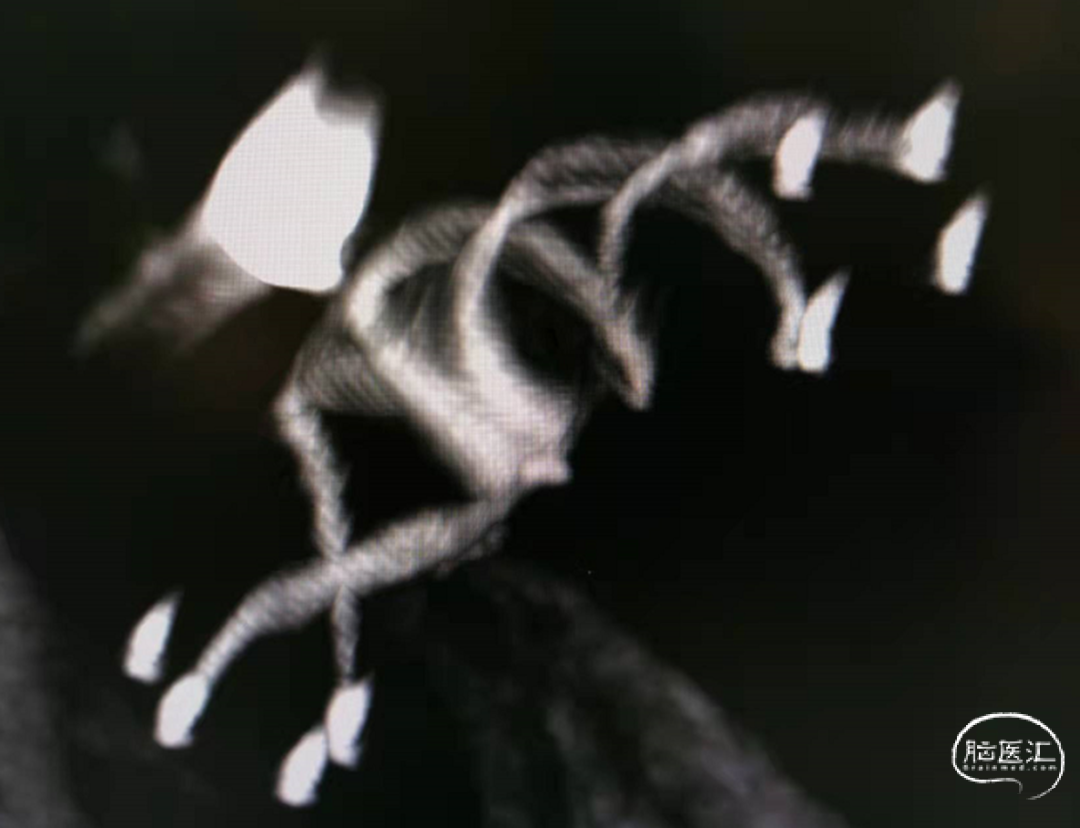

术后即刻支架形态

按摩后支架的形态

支架和弹簧圈重建的形态